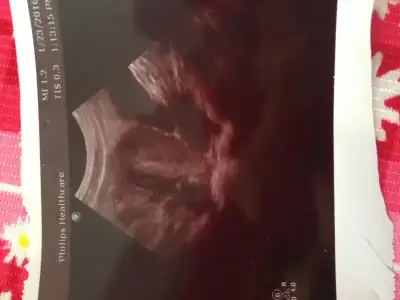

İlk kontrolümde 6 haftalıktı herşey yolunda dedi drum. 2 gün sonra hafif lekelenmem oldu gittim durumu söylememiş yanındaki sekreter kese var Bebek ve kalp atımı yok dedi. Bende haftaya gelecektim kalp için durum böyle dedim. Erken o Zaman dedi perşembe gel dedi. Baya tedirgin oldum. İnş bi sorun olmaz. O kadar uzun yoldan geldiki elim yüreğimde resmen.